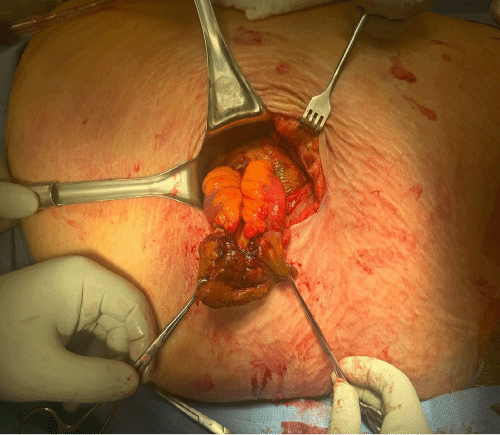

Given these findings, the patient was taken emergently to the operating room. A left-sided Wayne pigtail catheter was initially placed into the pleural space for decompression, yielding an immediate return of approximately 3,000 mL of succus entericus (Figure 4A), confirming a pleural effusion entericus. Correct intrapleural placement of the catheter was verified. Subsequently, the hernia sac was explored via a left flank incision. This revealed a 5 cm rupture of the hernia sac containing a strangulated and perforated loop of small bowel. Enteric contents were observed draining from this perforation into the abdominal wall planes and tracking superiorly through fascial defects into the pleural space (Figure 4B). The necrotic segment of small bowel was resected, and intestinal continuity was restored with a stapled anastomosis; the repaired bowel was then returned to the peritoneal cavity. A diagnostic laparoscopy was performed, which confirmed the absence of any primary diaphragmatic defect, further intraperitoneal bowel ischemia, or gross peritoneal contamination. Further exploration of the abdominal wall revealed that the chronic, large left flank hernia had significantly distorted the normal anatomical planes, including the fascial and muscular connections with the diaphragm and chest wall. This distorted anatomy likely facilitated the upward tracking of the succus entericus from the extraperitoneal perforation along the path of least resistance into the pleural space, as depicted on the CT images (Figure 3). This abnormal abdominal wall-to-pleural communication was also visualized thoracoscopically using a 30-degree scope.

Intraoperative photograph during exploration of the left flank hernia, revealing a loop of necrotic, strangulated small bowel protruding through a defect in the hernia sac